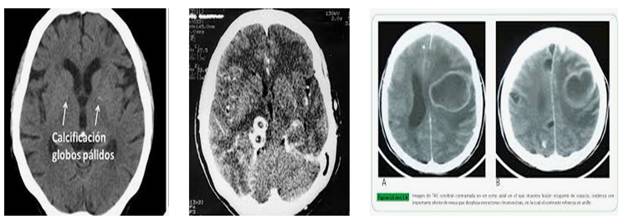

Hình 9

Trong số bệnh nhân, có 84,6% số ca là sinh ở nước ngoài và 62% có di cư từ Mexico. Có 33 người sinh tại Mỹ tử vong do ATSDL và tỷ lệ tử vong do ATSDL cao nhất ở California, chiếm 60% trong số ca tử vong do ATSDL. Sán dây lợn phổ biến ở châu Á, các quốc gia ở khu vực cận sa mạc Sahara, châu Phi và Mỹ Latin. Tại một số vùng, người ta cho rằng có đến 25% số ca bị ảnh hưởng, trong khi đó tại các quốc gia đã phát triển thì rất hiếm ca bệnh ghi nhận.

Vào năm 2015, trên toàn cầu bệnh SD/ATSDL gây ra khoảng 400 ca tử vong, trong đó ATSDL cũng ảnh hưởng lên lợn và bò, nhưng hiếm khi gây ra các triệu chứng và thời gian sống không dài. Bệnh thường xảy ra ở người trong lịch sử và dến nay vẫn còn tiếp diễn, song đây được ghi nhận là một trong các căn bệnh nhiệt đới bị lãng quên.